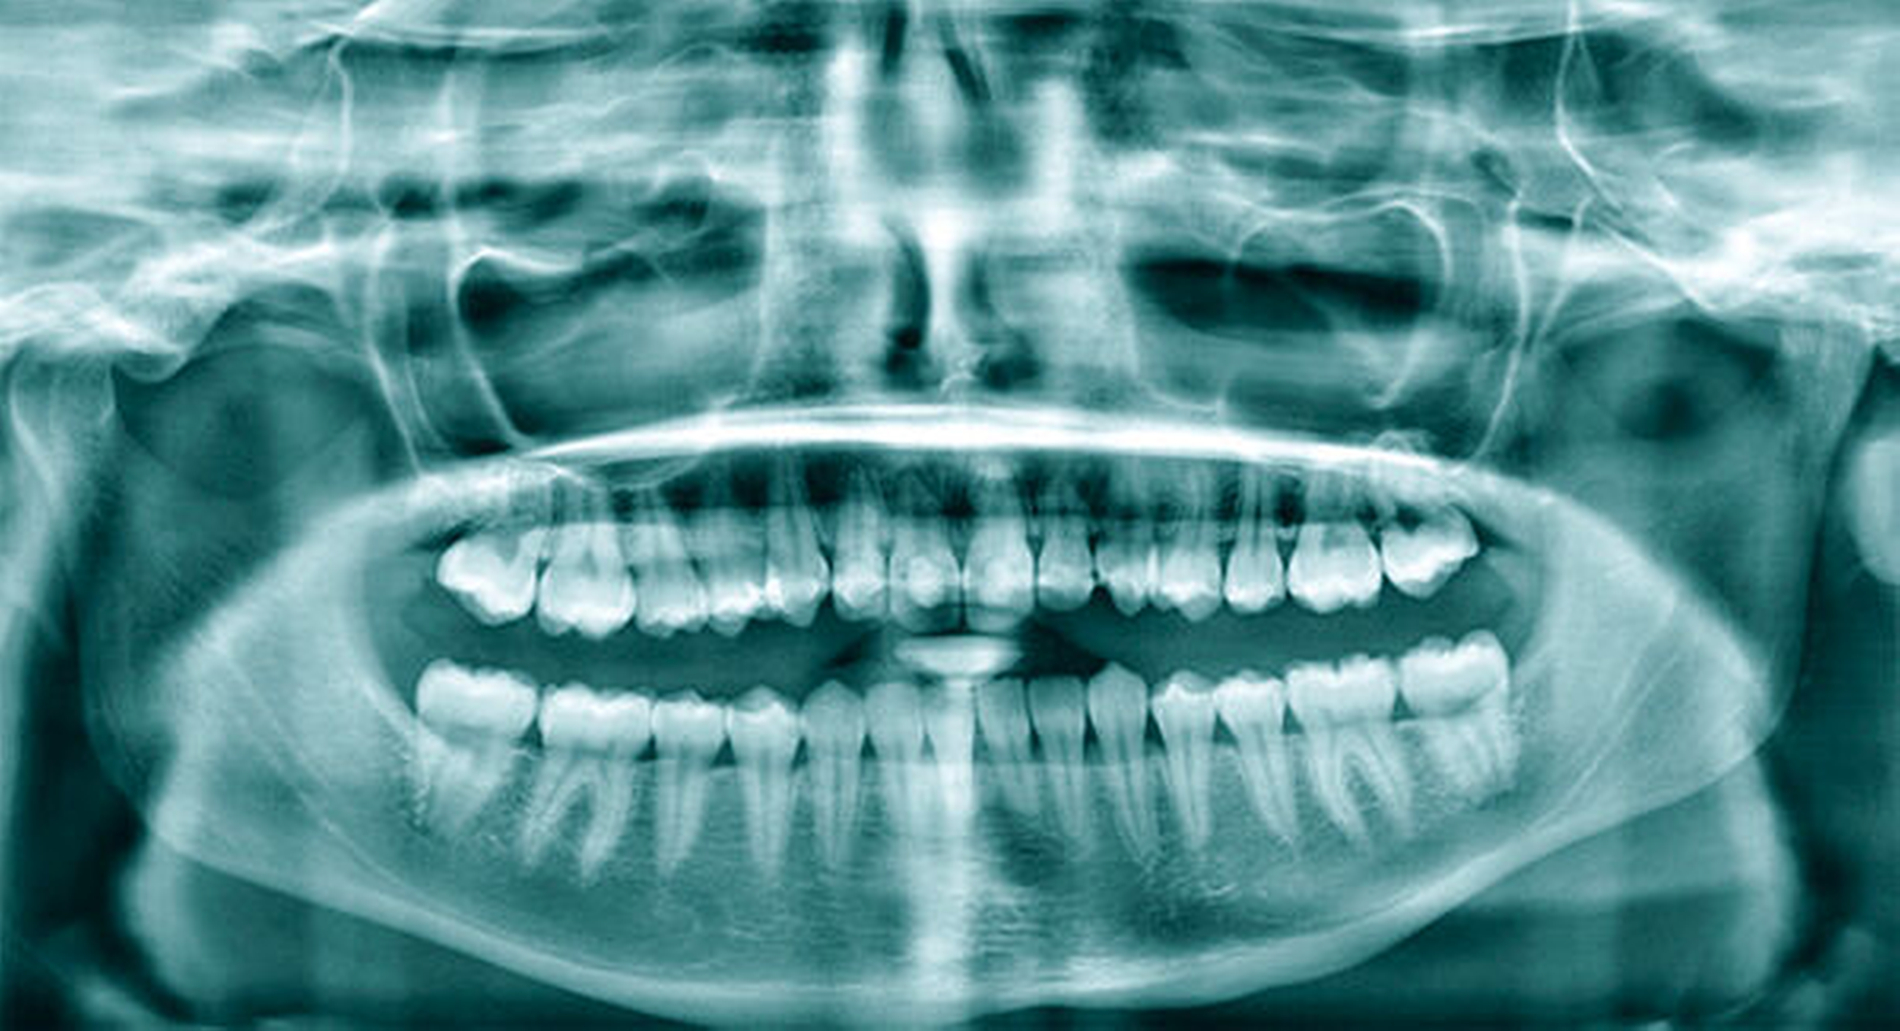

Aufgrund des Unfallmechanismus wurde ergänzend eine Computertomografie der Kopf-Hals-Region veranlasst (Abbildung 2), die lediglich minimale ossäre Begleitschäden der involvierten Zahnfächer nachwies. Weitere ossäre Traumafolgen und eine akute intrakranielle Blutung konnten somit ausgeschlossen werden. Das OPTG (Abbildung 3) zeigte die leeren Zahnfächer 12, 11, 21. Die übrigen Zähne wurden durch den Sturz nicht beschädigt. Mit Zustimmung der Patientin wurde gemeinsam mit der diensthabenden Gastroenterologin ein endoskopischer Bergungsversuch der Zähne geplant, um diese möglichst zu replantieren.